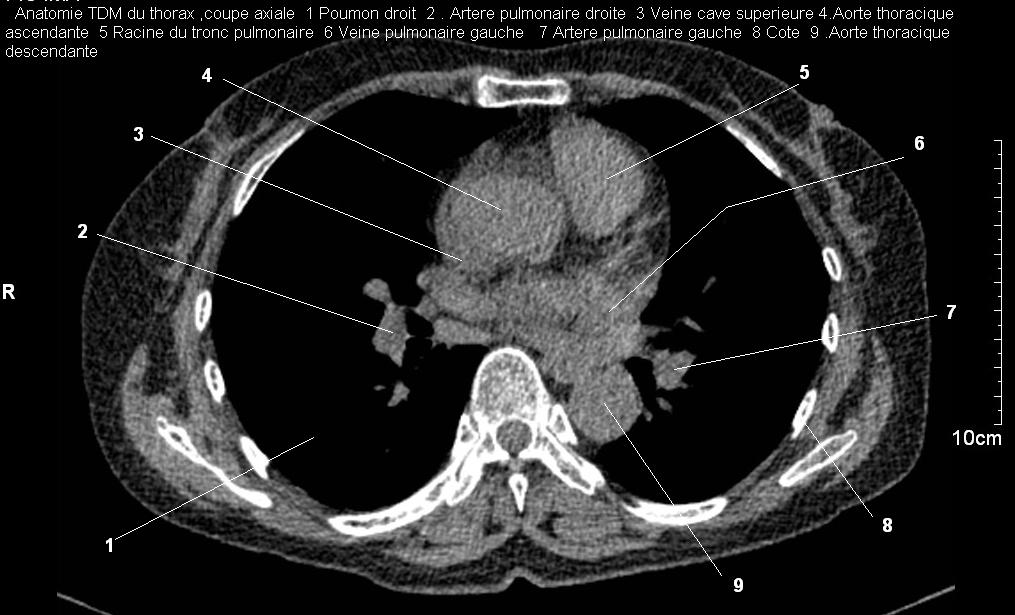

Image TDM normale du mediastin : Sur la TDM image

radiologique de mediastin en voyait très nette , en avant

est le sternum et sa jonction des côtes et en arrière c'est

la colone vertebrale .

Sa contenant est le cœur,

l'œsophage,

la trachée et

les deux bronches souches

, de gros vaisseaux

sanguins et lymphatiques,

ainsi que des nerfs

Imade radiologique TDM normale du

mediastin en coupe axiale à travers apical , et à

travers à supperieur de sinus Valsava de aort

ascendente . Le trache , les deux bronchous ,

vaiseaux de hile , des chaines ganglionaires et des

grands vaisseaux sont en vue et interpreter

facilement .